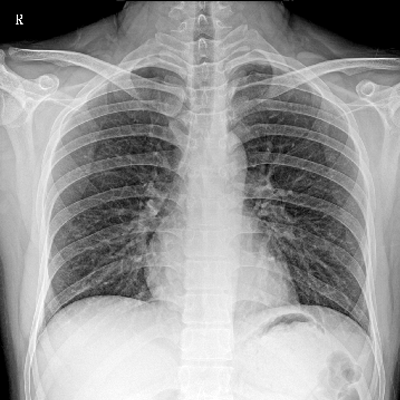

用于影像科、急診室、病房、ICU、手術(shù)室等多場(chǎng)景應(yīng)用。

● 數(shù)字化無(wú)線平板成像,操作簡(jiǎn)便,成像質(zhì)量高